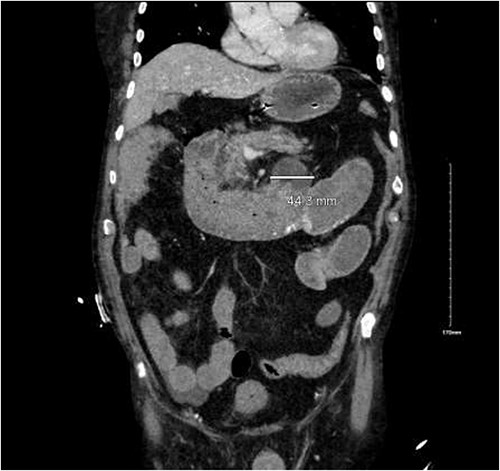

CTA demonstrated angiodysplasia in the duodenal diverticulum at the duodenojejunal junction with associated contrast blush (Figs 1 and 2). The urgent opinion of an interventional radiologist was sought in a tertiary centre. The patient was accepted for urgent embolization in an attempt to stabilize the patient. The patient required an intra-hospital transfer overnight.

The on-call interventional radiology team performed a successful embolization. A 6-French Sheath was passed through the left common femoral artery, and a 5-French Sim-1 catheter was advanced into the coeliac and common hepatic artery. A 2.4 French Direxon microcatheter was advanced into a branch of the superior mesenteric artery at the site of bleeding. Successful coil embolization with a 2 mm × 2 mm concerto micro coil was performed. A satisfactory angiographic result with DYNA-CT, also known as modern C-arm CT or cone-beam CTA, showed no extravasation.

There were no immediate complications to the procedure. The patient returned to intensive care post-operatively. He remained intubated and vital laboratory tests were stabilized. He experienced acute renal failure post-procedure that required haemodialysis and prolonged intubation (Figs 3 and 4).